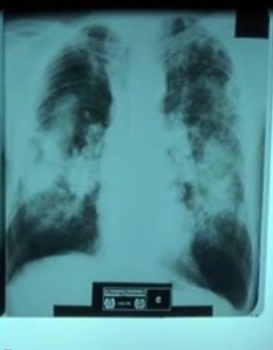

X-ray of silicosis lungs

X-ray of silicosis lungs.

Once the full effects of the rule are realized, OSHA estimates that the proposed rule would result in saving nearly 700 lives per year and prevent 1,600 new cases of silicosis annually. For more information on the proposed rule and how to participate in the rulemaking process, visit OSHA's silica rulemaking page at www.osha.gov/silica and read Dr. Michaels' new post on the DOL blog.